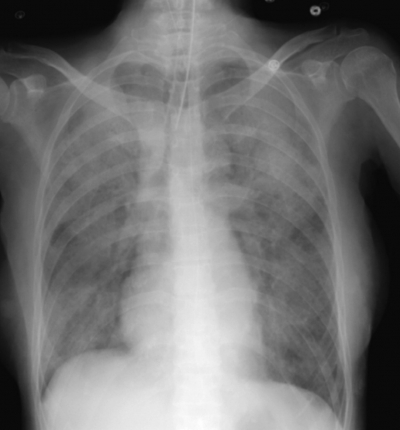

68歳の女性。腹膜炎の手術後でICUに入院中である。3日前に消化管穿孔による急性汎発性腹膜炎で緊急手術が行われた。術後は気管挿管されたままICUに入室し、人工呼吸管理を受けている。本日から呼吸状態が悪化し、気管からピンク色泡沫状の分泌物が吸引された。

心拍数 86/分、整。血圧 120/80 mmHg。動脈血ガス分析(FiO2 0.7):pH 7.32、PaCO2 42 Torr、PaO2 69 Torr、HCO3- 23 mEq/L。胸部エックス線写真を別に示す。心エコーで左室駆出率 60 %、左室壁運動に異常を認めない。有意な弁膜症を認めない。